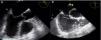

Transthoracic echocardiography: (a) anatomically normal image in parasternal short-axis view; (b) parasternal short-axis view showing parallel great vessels and morphologically right ventricle in anterior position in continuity with the aorta, also in anterior position (Video 1). Ao: aorta; AP: pulmonary artery; V. Morf. Dto: morphologically right ventricle.